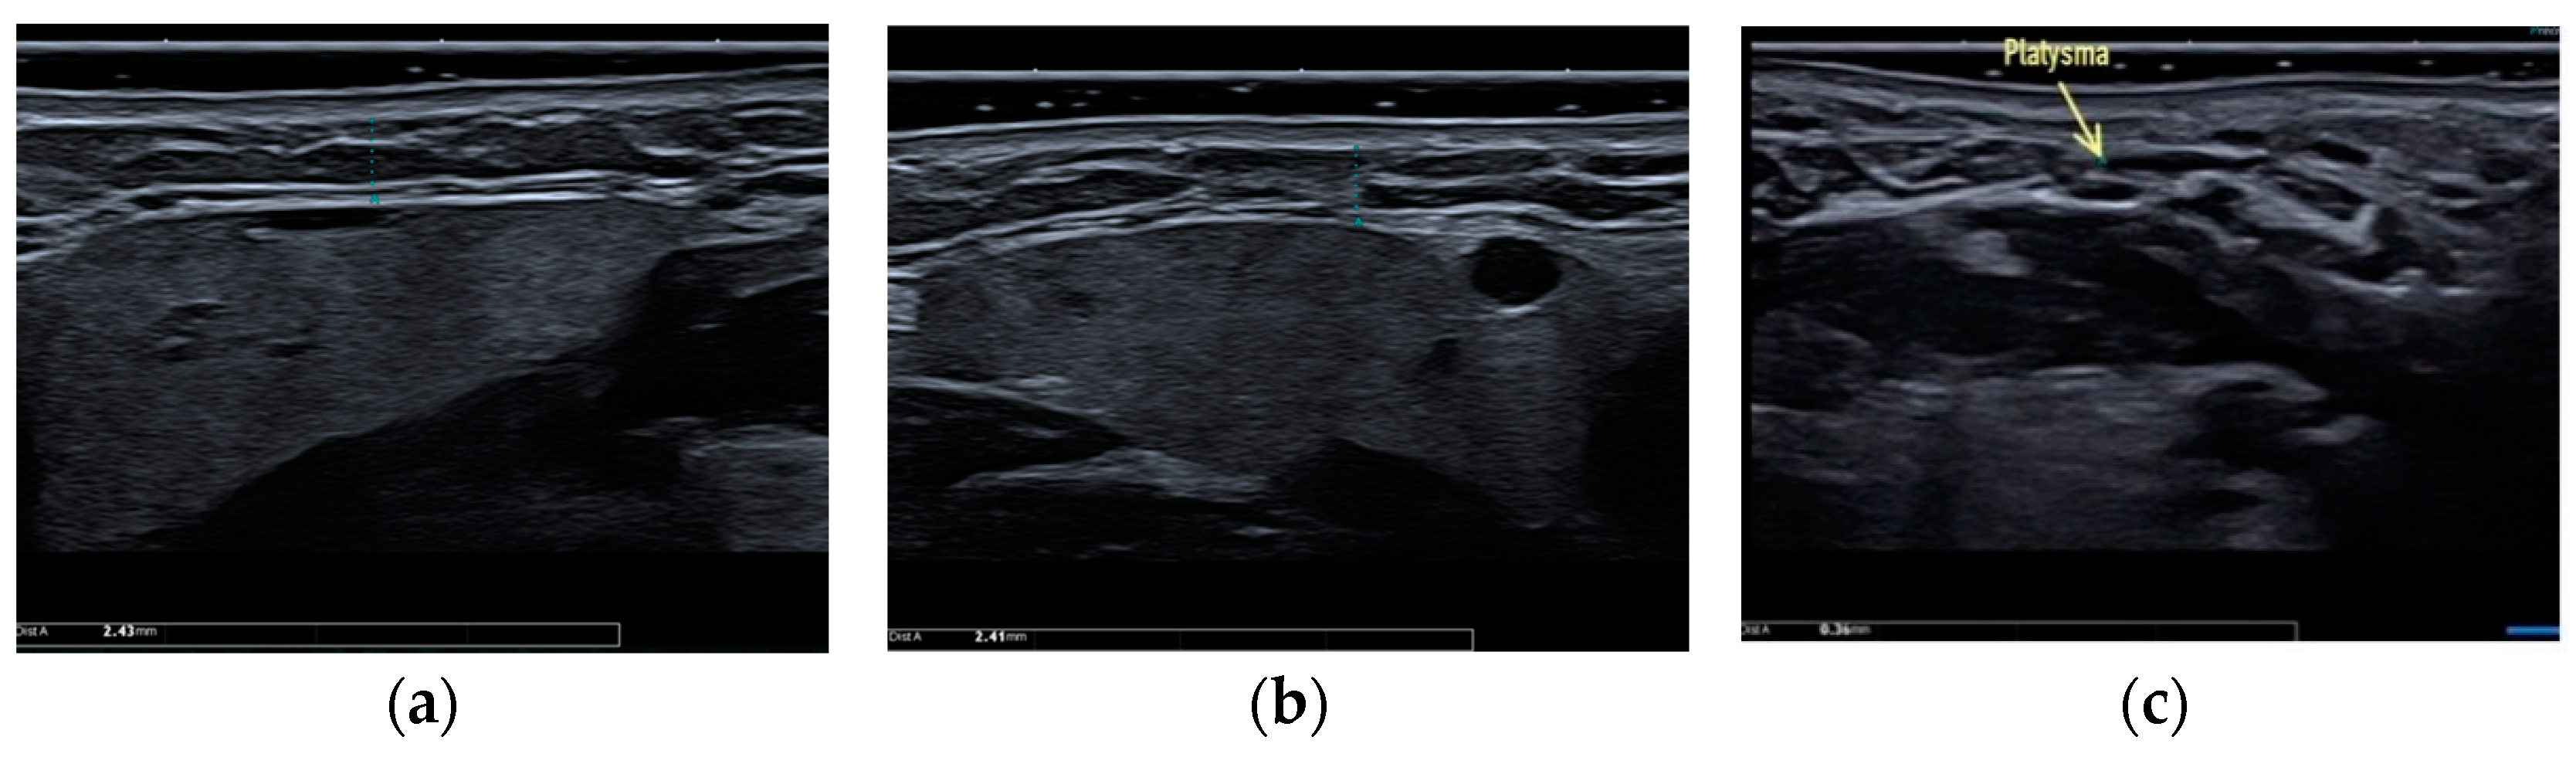

Clinical case #3. During the study, a 46-year-old female patient with a 24 MHz linear transducer of soft tissues of the lower third of the face and neck without pressure, in an upright position, exhibited the absence of the accumulation of adipose tissue along the contour of the lower jaw from two sides (Figure 3a,b) and sagging of a rather thin platysma (diameter 0.36 mm), causing age-related contour deformities (Figure 3c).

Figure 3.

B-mode ultrasound examination of the soft tissues of the lower face and submandibular area with a 24 MHz linear transducer. Absence of the accumulation of adipose tissue along the contour of the lower jaw from both sides (a,b), and sagging platysma causes age-related contour deformities (c).

Accordingly, it is correct to direct the efforts of a plastic surgeon to the correction of ptotic platysma in the presented clinical case, which will be sufficient to obtain a good clinical result.